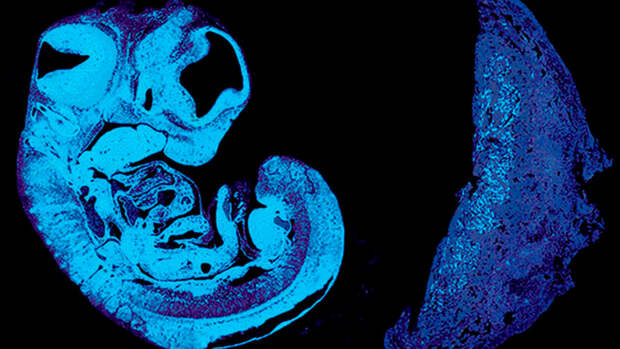

Ионел Сандовичи и его коллеги из Кэмбриджского университета провели опыты на мышах, в которых изучали влияние разных генов на развитие зародыша в матке.

По мере роста плода, ему требуется все больше и больше питательных веществ, и об этом необходимо как-то сообщить материнскому организму. Питательные вещества поступают в ребенка через плаценту, особый орган, который связан с ним через пуповину и закреплен на стенках матки.

Ученые выяснили, что плод заставляет передавать все больше и больше питательных веществ с помощью вещества IGF2, которое достигает плаценты через пуповину. У людей уровень IGF2 в пуповине постепенно увеличивается начиная с 29 недели и до рождения. Более высокие уровни этого вещества ассоциируются с избыточным ростом плода (что тоже вредно), а более низкие – с недостаточным.